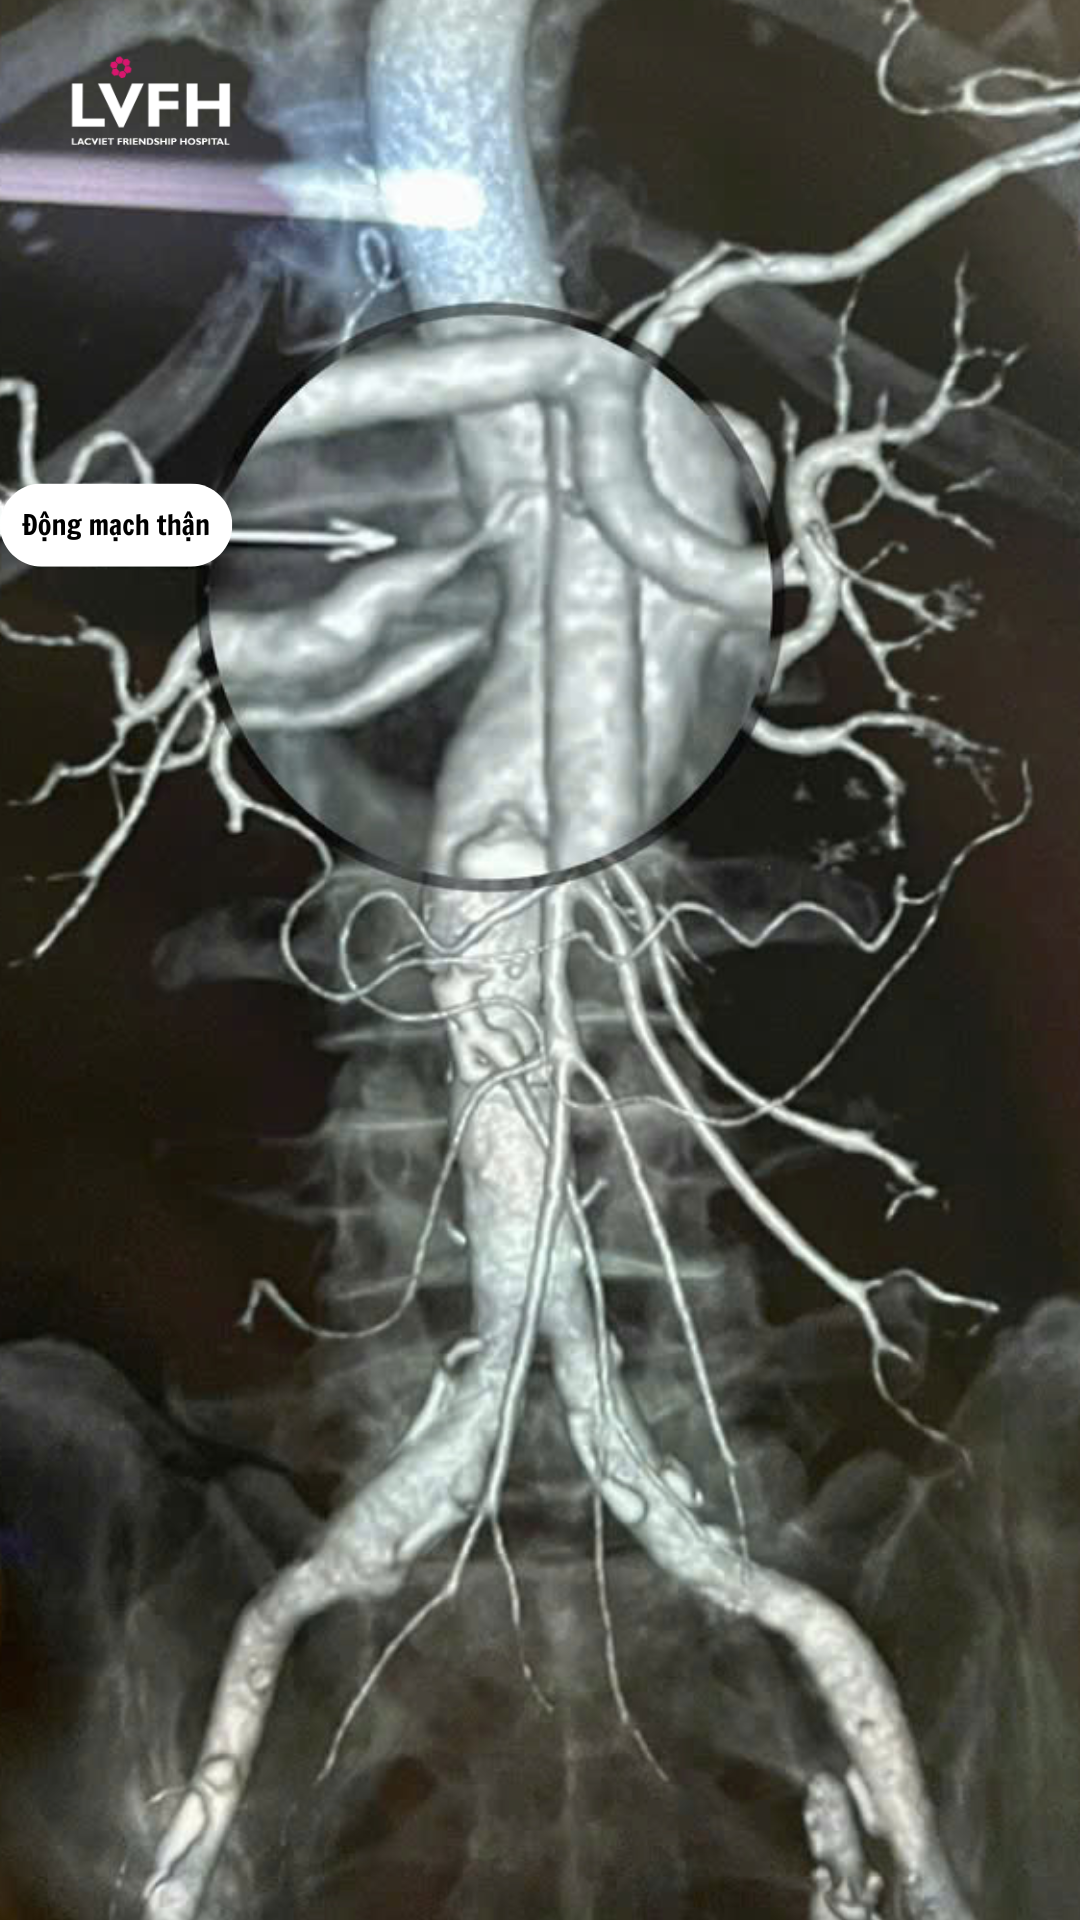

Hình ảnh bệnh nhân tổn thương hẹp khoảng 70% động mạch thận phải ngay đoạn xuất phát.

Nhờ máy CT Scanner 128 dãy tại Bệnh viện Hữu Nghị Lạc Việt, tổn thương hẹp khoảng 70% động mạch thận phải ngay đoạn xuất phát của bênh nhân T.T.H (63 tuổi, Yên Lạc – Phú Thọ) đã được phát hiện, dựng hình rõ nét và đánh giá chính xác mức độ nguy hiểm, kịp thời.